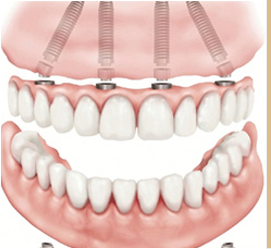

全口植入8颗

半口植入4颗

可以解决全口、半口无牙颌、 牙槽骨严重萎缩/极薄问题。

ICX种拥有很高的灵活性,面对长期半颌和全颌重度骨缺损也能理想修复。ICX全颌新的multi全颌修复方案,在短短的1-2小时内即可完成手术,避免了长期复杂的骨移植手术,大大减少了手术创伤,节省了治疗费用。